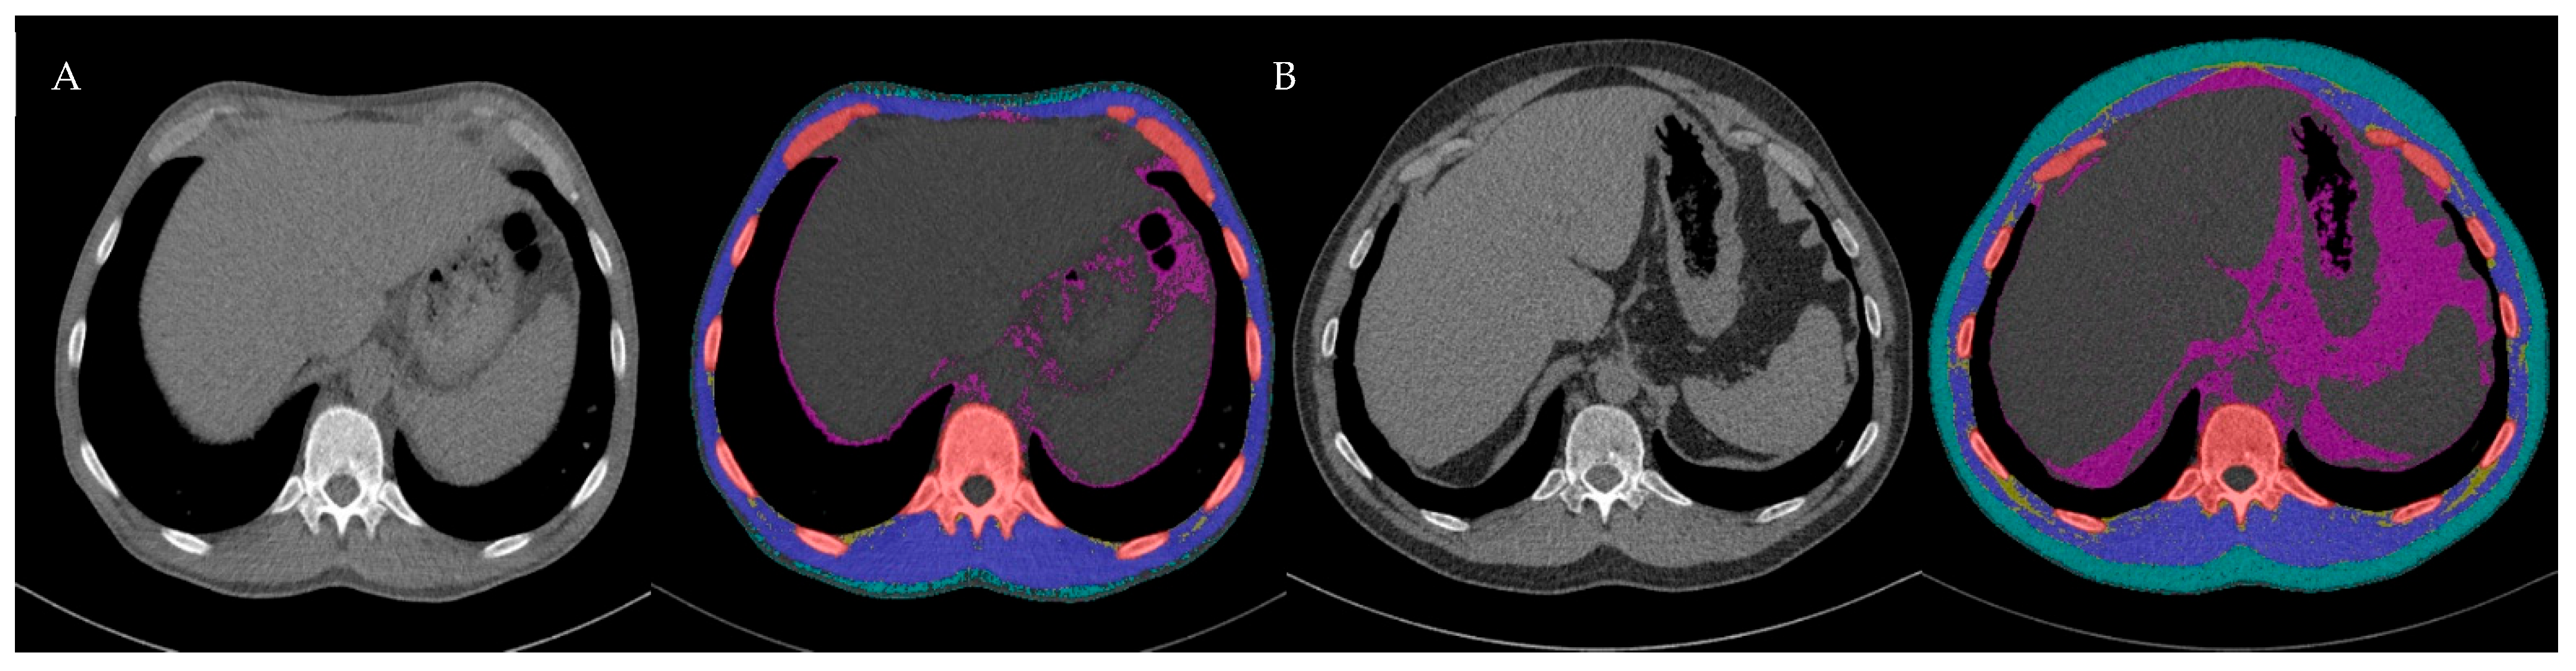

PwCF were scanned in an inspiratory breath-hold and head-first supine position with their arms elevated. For further image processing, reconstruction in the soft tissue window B31F with a 1 mm slice thickness was used to perform body composition analysis (BCA). BCA is a component of an open-source body organ analysis (BOA) platform [25,26]. This technique combines various segmentation methods and prioritizes an efficient workflow by incorporating DICOM node functionality. It also enables highly precise automatic tissue segmentation independent of dose-related scan parameters [27]. In addition to tissue-specific segmentations, the model computes volumetric and density-dependent features, providing a comprehensive three-dimensional characterization of the body composition. To complement the volumetric analysis, the BOA model performs cross-sectional segmentation. In this study, only cross-sectional segmentation from the median slice of the T12 vertebral body was extracted to ensure a consistent anatomical reference point for comparability between patients (Figure 1).

Figure 1. Cross-sectional CT images illustrating AI-derived body composition analysis (BCA) at the T12 level and its changes over time. Bone (red), muscle (blue), visceral adipose tissue (purple), subcutaneous adipose tissue (turquoise), and IMAT (yellow). (A) Pre ETI: SMA 92.5 cm2, IMAT 4.0 cm2, IMAT/SMA 4.3%; (B) post-ETI: SMA 120.2 cm2, IMAT 19.6 cm2, IMAT/SMA 16.3%. ETI, elexacaftor, tezacaftor, ivacaftor; SMA, skeletal muscle area; IMAT, intermuscular and intramuscular adipose tissue; LAMA, low-attenuation muscle area.